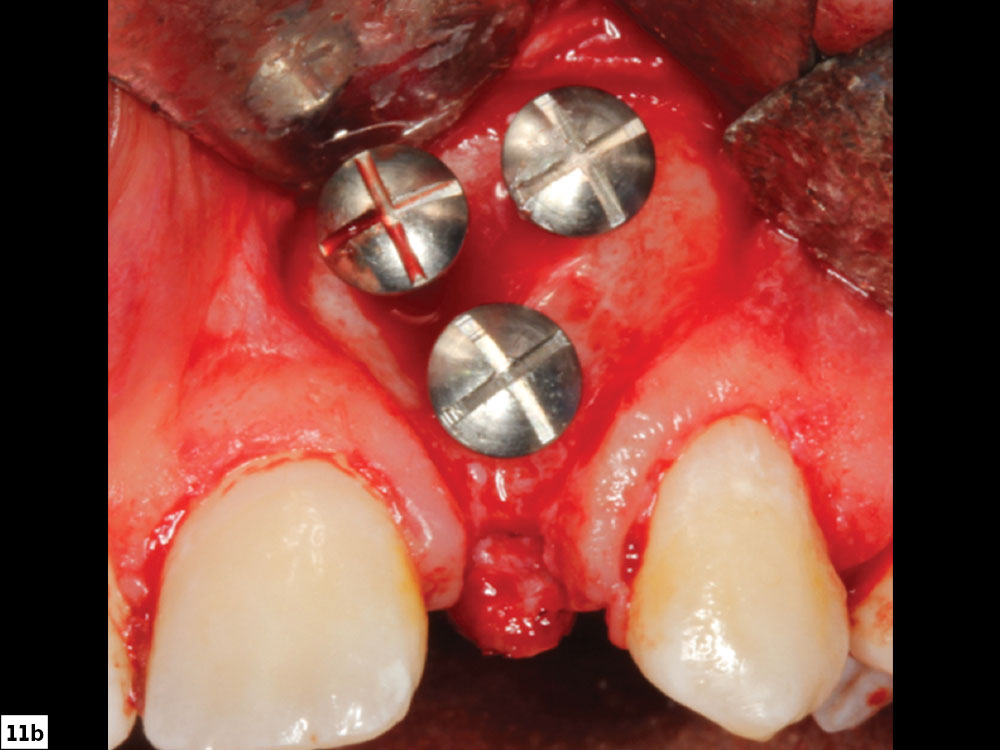

Positioning of Tenting Screws

The positioning of the screws should be planned in a manner that will result in a dome shape that is formed by the heads of the screws, which should match the intended contour of the final ridge form. The use of multiple screws in this technique creates very specific ridge forms that cannot be attained with unsupported membranes. Usually, screws are placed in a nonparallel fashion approximately 3–4 mm apart, which allows sufficient space for angiogenesis to occur. The location and trajectory of adjacent tooth roots must be determined to prevent screw placement near a tooth root. Ideally, intraoperative radiographs should be taken to verify ideal positioning in relation to tooth root position (Figs. 11a, 11b).

Large-head tenting screw

Tenting screw positioning on site

Figures 11a, 11b: Large-head tenting screw (11a); tenting screw positioning (11b).